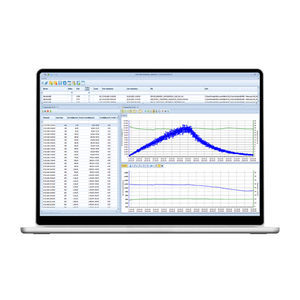

... El software Office Medic mejora el flujo de trabajo al disponer de una única plataforma para las pruebas de ECG y espirometría. Office Medic permite adquirir, almacenar y revisar datos de diagnóstico utilizando un ordenador ...